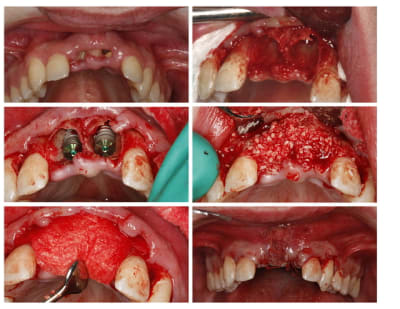

Ce cas est limite et aurait pu être traité en deux temps mais bon, j'ai opté pour y aller franco...

La seamine prochaine je vous montrerai la finition céramique.

Bon la suite des photos mais il faut commencer par la dernière, l'ordre de passage lors de l'envoi s'est apparemment inversé...

Zut, l'ordre des photos n'est pas celui que j'avais prévu, vous voudrez bien remettre dams l'ordre en lisant les titres. Le logiciel d'eugénol mélange tout à sa guise...

o.k. mais le trip reste le même que tu le fasses en une fois ou huit jours après. La bague de cica est déjà une mise en vitrine. D'autre part ce genre de truc ça gonfle tellement les premiers jours que ta patiente ne va pas sourire des masses ni même bouffer dans le secteur... Il faut relativiser d'autant plus qu'ici je me retrouvais short pour le calage primaire et tu noteras la classe II... La mise en place de la provisoire a eu lieu au retrait des sutures. Et il ne pourra pas s'agir d'une mise en charge, simplement d'une mise en vitrine.

Le didacticiel répondait à la question de Pluton qui se rendra vite compte que la mise en vitrine immédiate en zone prémaxillaire est un objectif peut-être souvent poursuivi mais plus rarement atteint. Mais peut-être qu'ailleurs l'herbe est plus verte ?